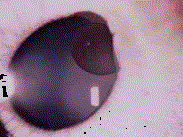

问题 患者,男,诉左眼胀痛,检查左眼视力0.8,裂隙灯检查如图,对该病描述正确的是 ( )

选项 A、以外伤植入性最常见 B、多采用YAG激光术治疗 C、眼球穿通伤或内眼手术后,结膜或角膜上皮通过伤口进入前房,种植于虹膜 D、由于虹膜色素上皮过度增生 E、囊肿不断增生,引起青光眼

答案 ABCE